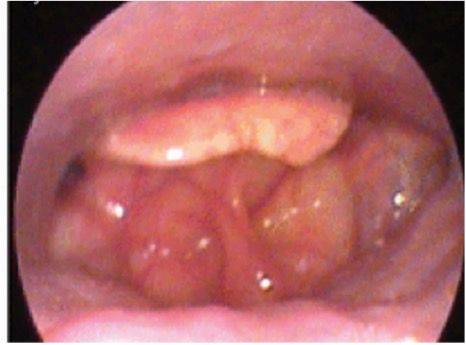

La Drug-induced sleep endoscopy (DISE) è una procedura diagnostica adatta alla valutazione dinamica delle vie aeree superiori inducendo un sonno simile a quello naturale che consenta di fornire una accurata rappresentazione delle vie aeree superiori diversa da quella della visita con paziente sveglio.

La DISE può evidenziare un collasso dell’epiglottide non visibile nelle sezioni di visita da svegli. Tale condizione è certamente sottostimata con la visita ambulatoriale da svegli ed il suo riconoscimento è particolarmente importante per la pianificazione ed il successo della terapia chirurgica.

Il collasso dell’Epiglottide ha una incidenza estremamente variabile nell’OSA (11.5% – 73.5%) a seconda dei criteri diagnostici utilizzati. La classificazione VOTE suddivide il collasso in antero posteriore e laterale. Esistono altri sistemi classificativi: The Francia–Lugo classification ricavata dall’esame di oltre 600 soggetti sintetizza il collasso in (1) collasso primario (76%), che include collasso antero posteriore con una epiglottide rigida (trapdoor)

e collasso antero posteriore con una epiglottide fluttuante (floppy)

e collasso latero-laterale con una epiglottide ad omega (book)

e (2) collasso dell’epiglottide secondario (24%), risultante dalla compressione delle strutture adiacenti.

La classificazione DISE, di più facile applicazione distingue un prolassamento antero-posteriore, un depiazzamento posteriore ed una flessione laterale